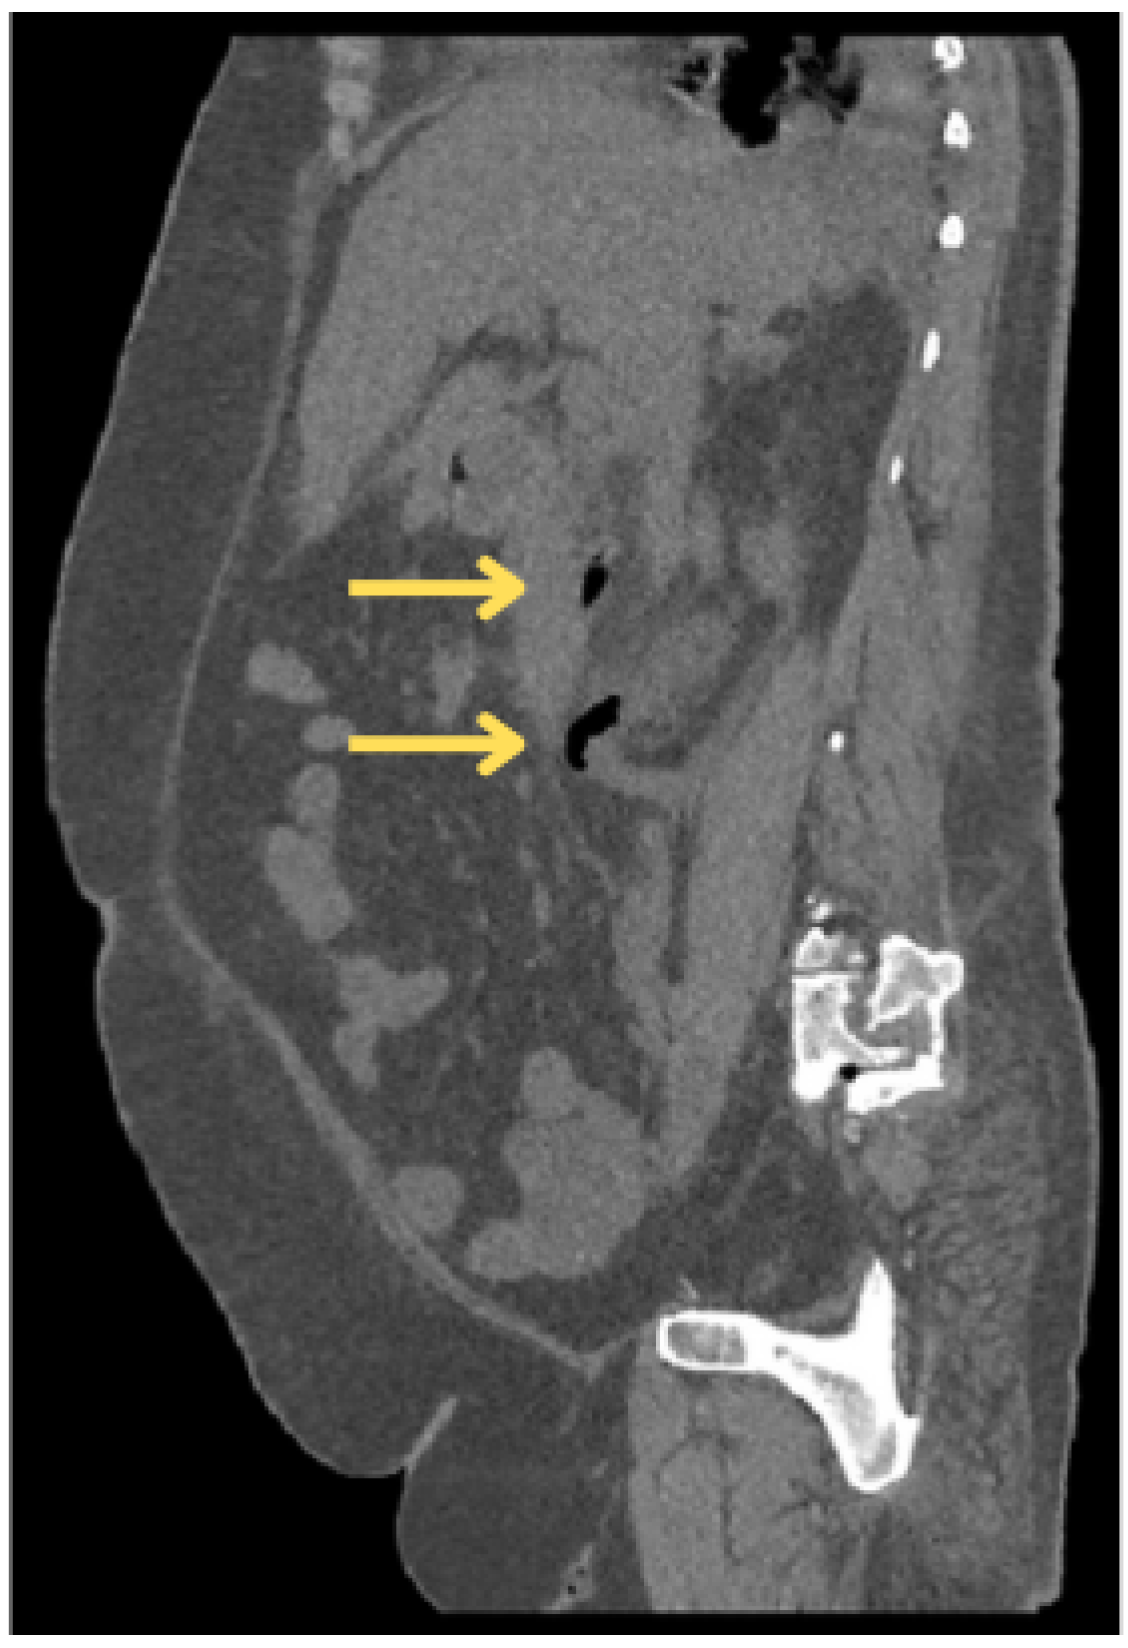

2.3. Diagnostic Findings

| CECT | Contrast-enhanced computed tomography |